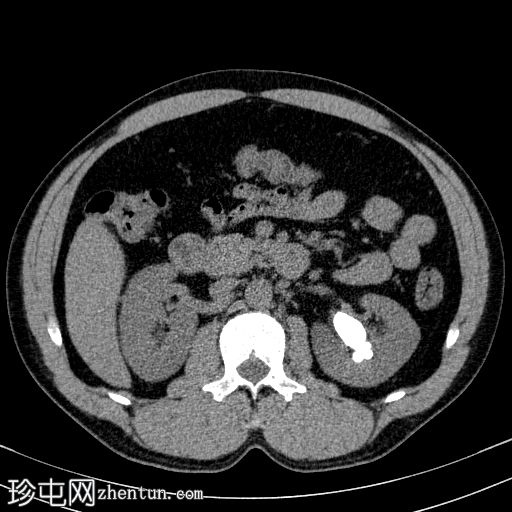

CT

轴位

平扫

左侧肾盂内可见一鹿角状结石,延伸至肾盏系统,平均CT值约为1200 HU。

右肾可见数枚微小结石,最大一枚位于肾下盏,直径约2 mm。这些结石未引起任何梗阻性改变。